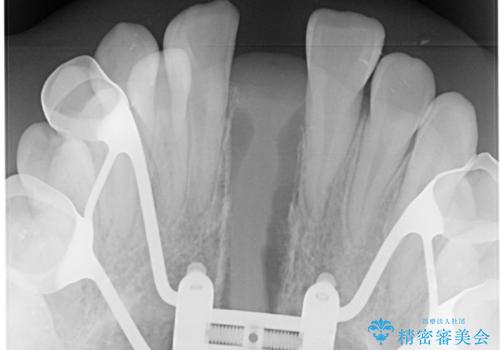

MARPEについて

MARPE(Mini screw assisted rapid palatal expansion )は、上顎の幅を広げる矯正治療です。

歯だけでなく、あごの骨に直接力をかけて広げるのが特徴です。

これまで難しかった大人の方でも、上あごの拡大が可能な場合があります。

上顎の骨に小さなネジ(マイクロインプラント)を使用し、装置をしっかり固定します。

その力で上あごの正中(真ん中の骨のつなぎ目)を少しずつ広げていきます。